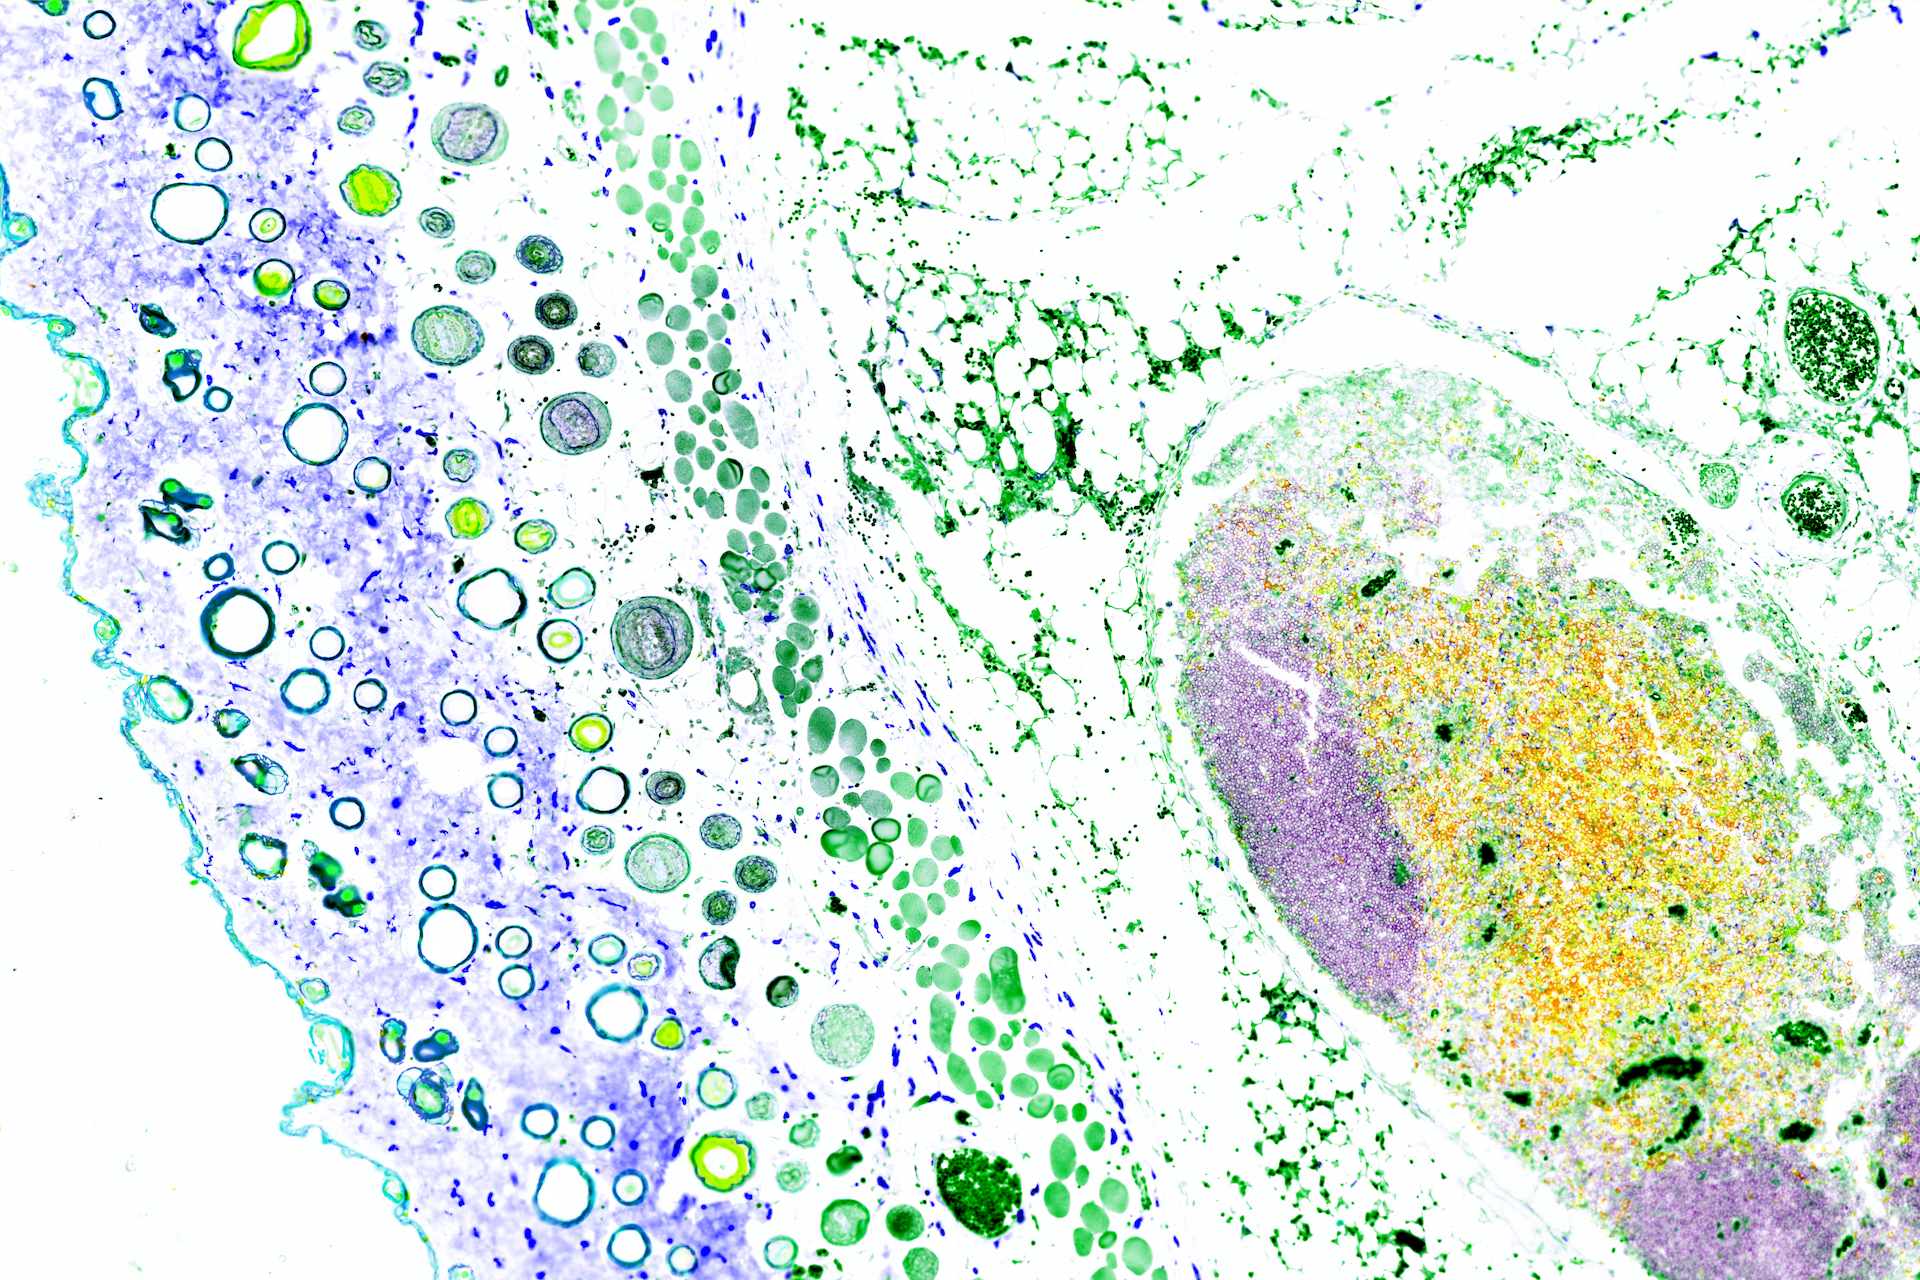

Revealing the hidden beauty of immune cells, these stunning microscopy images bring to life the intricate world of immune cells. The images dispatch us through the lens of a powerful microscope into real tissue structures, where we land amidst immune cells at work. Each colorful panorama is the product of researchers delicately staining a tissue sample and then digitally altering the visuals to differentiate between the tissue structures and immune cells.

Here, you’ll witness how researchers at La Jolla Institute for Immunology explore the secrets of the immune system, one microscopic detail at a time—in real time. Thanks to a generous gift from Michael and Ellise Coit, our Microscopy and Histology Core Facilities acquired an advanced multiplex imaging technology, enabling LJI scientists to study the immune system’s response to cancers, autoimmune diseases, and infectious diseases.